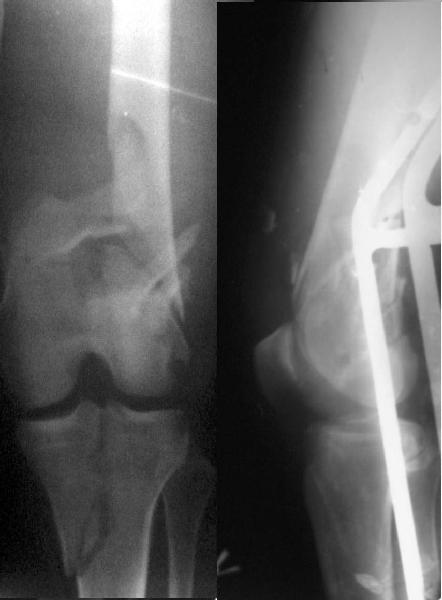

This is what we have done... As generally true for LISS look at the bone not the hardware.

There are two more srews above. The one not completely in got damaged head.